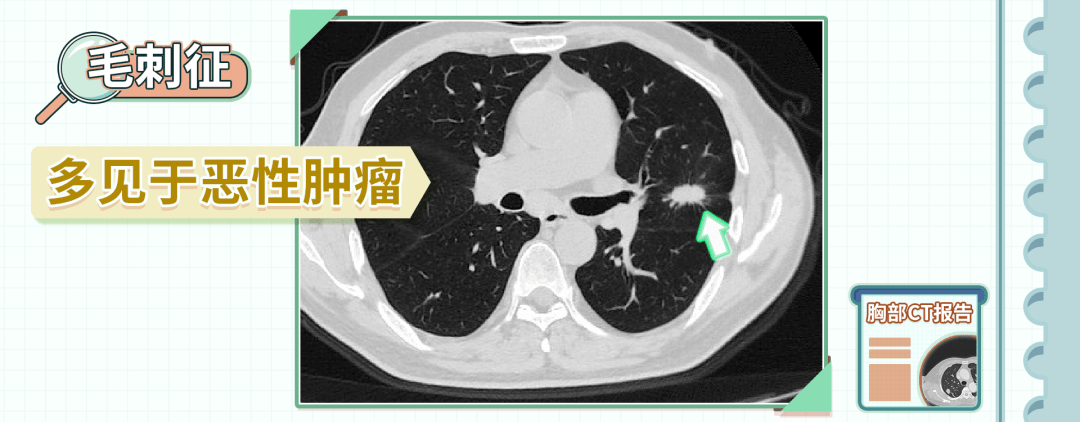

一看大小,二看形态,两招判断"肺结节"的良恶性!_肿瘤